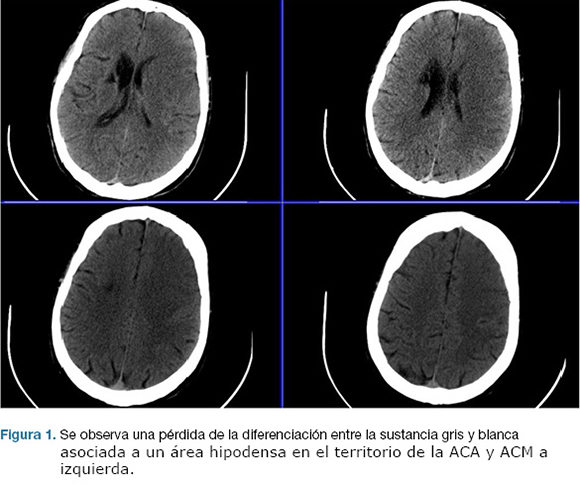

Se realizo TC de cráneo, que confirma área de isquemia en territorio de la arteria cerebral media (ACM) y arteria cerebral anterior (ACA) izquierda. (Figura 1). No se realizó fibrinolíticos intravenosos por encontrarse fuera de los plazos de tiempo. A las 17 horas de la evolución deprime conciencia, constatándose apertura ocular al llamado, no cumple órdenes, mutismo afásico, CGS: 9. Se reitera TC de cráneo que evidenció un aumento extenso del área de infarto de la ACM, y ACA, con efecto de masa dado severo. (Figura 2)